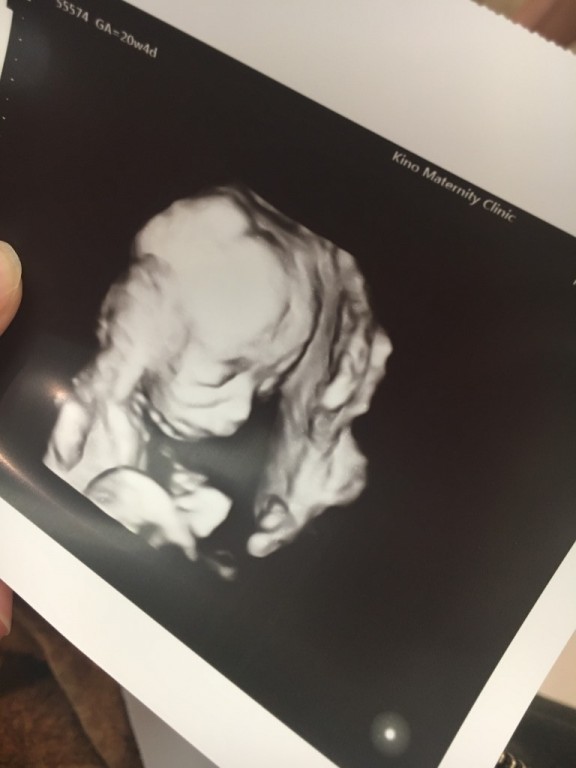

妊娠5ヶ月 20週0日 撮影日:2019年08月23日

目鼻立ちがハッキリ!顔つきからして男の子かな?なんて思ってますが、まだ分からず。腰の痛みが辛くなっていて、骨盤サポートベルトを探している最中です。